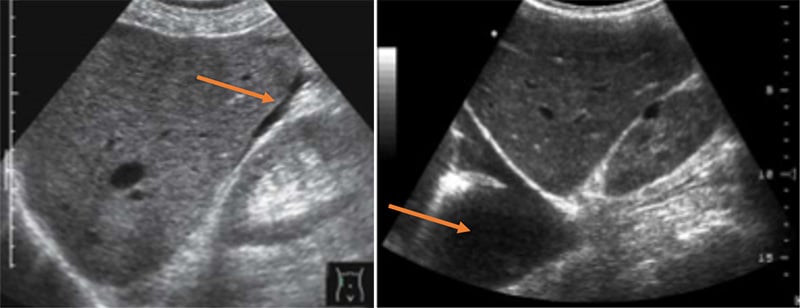

Figure 54A. Transverse views of the liver revealing moderate periportal fibrosis. Note the thickened hyperechoic walls surrounding the portal vein and branches.

Figure 54B. Transverse views of the liver revealing moderate periportal fibrosis. Note the thickened hyperechoic walls surrounding the portal vein and branches.